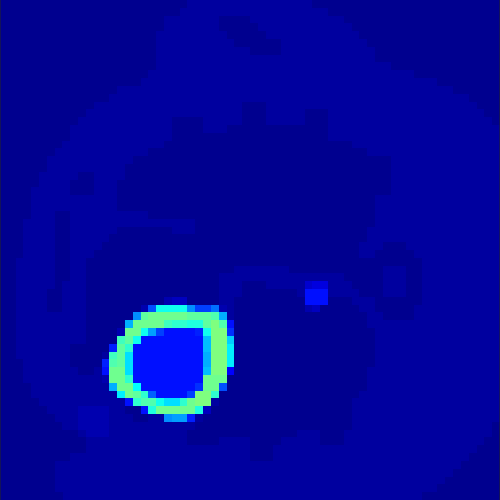

5.2 Monte Carlo Simulation

In order to test the behaviour of the proposed method in a more realistic, random-based test case, we performed a Monte Carlo simulation for dynamic SPECT imaging. First, we created a simple image phantom consisting of an outer and two inner circles which represents the structure of the region of interest (see figure 8(a)). Within those regions we assumed concentration curves over a time period of 90 time steps as displayed in figure 8(b). Based on the tracer intensity in an image frame at each time step, we created a variable number of random decay events (where the number is proportional to the average concentration in one pixel in the whole image frame per time step) with a probability proportional to the concentration in every subregion. They are detected by a virtual double head gamma camera rotating around the patient by 46 degrees per time step, which consists of 374 detector bins. Every simulated decay event is projected onto the scanner and counted by the corresponding detector bin.

In two different tests we fixed the number of events counted by the detector equal to (resp. ) times the average concentration in one pixel. The resulting sinogram images of the accumulated counts in each bin are shown in figure 9.

Based on the sinogram data we applied the proposed algorithm in order to reconstruct the original image sequence. The results for both test cases are shown in figure 10.

As one can see, the method is able to reconstruct the regions properly, even in case of a low count number. Within a number of iterations (average of 100 outer and 10000 inner iterations), the algorithm presents a reasonable reconstruction of the region of interest and the corresponding regional tracer concentration curves. Here, the parameters were not optimized as in the case of the synthesized data sets in the previous section, but kept fixed as , and . With futher optimized parameter values one could possibly provide even better results.